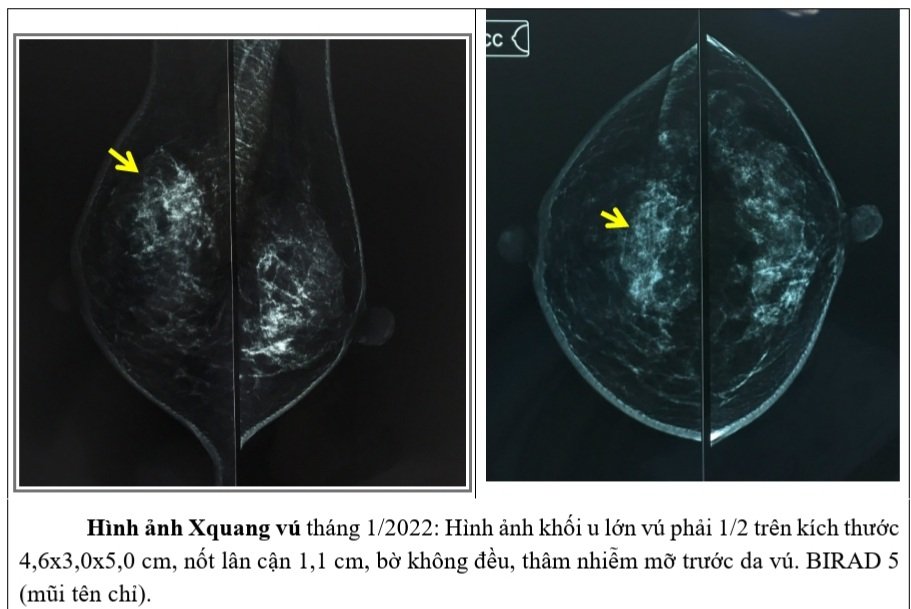

– Xquang vú: Hình ảnh khối u lớn vú phải 1/2 trên kích thước 4,6×3,0x5,0 cm, nốt lân cận 1,1 cm, bờ không đều, thâm nhiễm mỡ trước da vú. BIRAD 5.